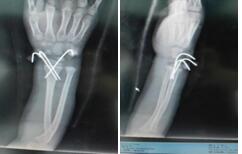

手术治疗:

手术治疗的注意事项:

(1)定期换药:对手术切口要每3-4天左右换一次药。对外露的针尾、外架,要每日碘伏消毒,针尾应暴露,避免覆盖。出现明显红肿、分泌物要及时就医。

(2) 手术虽有内固定,外固定也要确实,儿童骨折固定的原则要求"稀疏的内固定,坚强的外固定"。所以家长要经常查看外固定的石膏或支具、外露的外架或针尾是否有断裂、松动,如果出现要及时回医院调整。